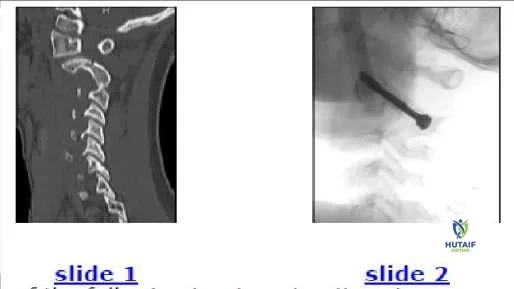

The 7-year-old patient shown in this image (Slide 1) is most likely presenting with:

Correct Answer: Fracture and subluxation

This patient has a spondylolisthesis of the axis, which is also known as a Hangmanâ s fracture. Additionally, a subluxation of the C 2-C 3 facet is present on the right side. Such a subluxation often accompanies a Hangmans fracture. The comparison image (Slide 2) of the opposite facet is shown as a reference to demonstrate the normal alignment.

Which of the following treatment options is recommended for the patient shown in the image (Slide 1, Slide 2):

Correct Answer: Open reduction and internal fixation

Treatment must address the fracture of the C 2 pars interarticularis and the C 2-C 3 facet subluxation. Options include traction to reduce the subluxation followed by external immobilization, or open reduction of the facet subluxation, which includes the opportunity to internally fix the fracture. Traction failed in this patient because the fracture eliminates a means to pull

on the arch of C 2. If facet subluxation is not present, then a cervicothoracic orthosis such as a Philadelphia collar is adequate for healing of the C 2 spondylolysis.